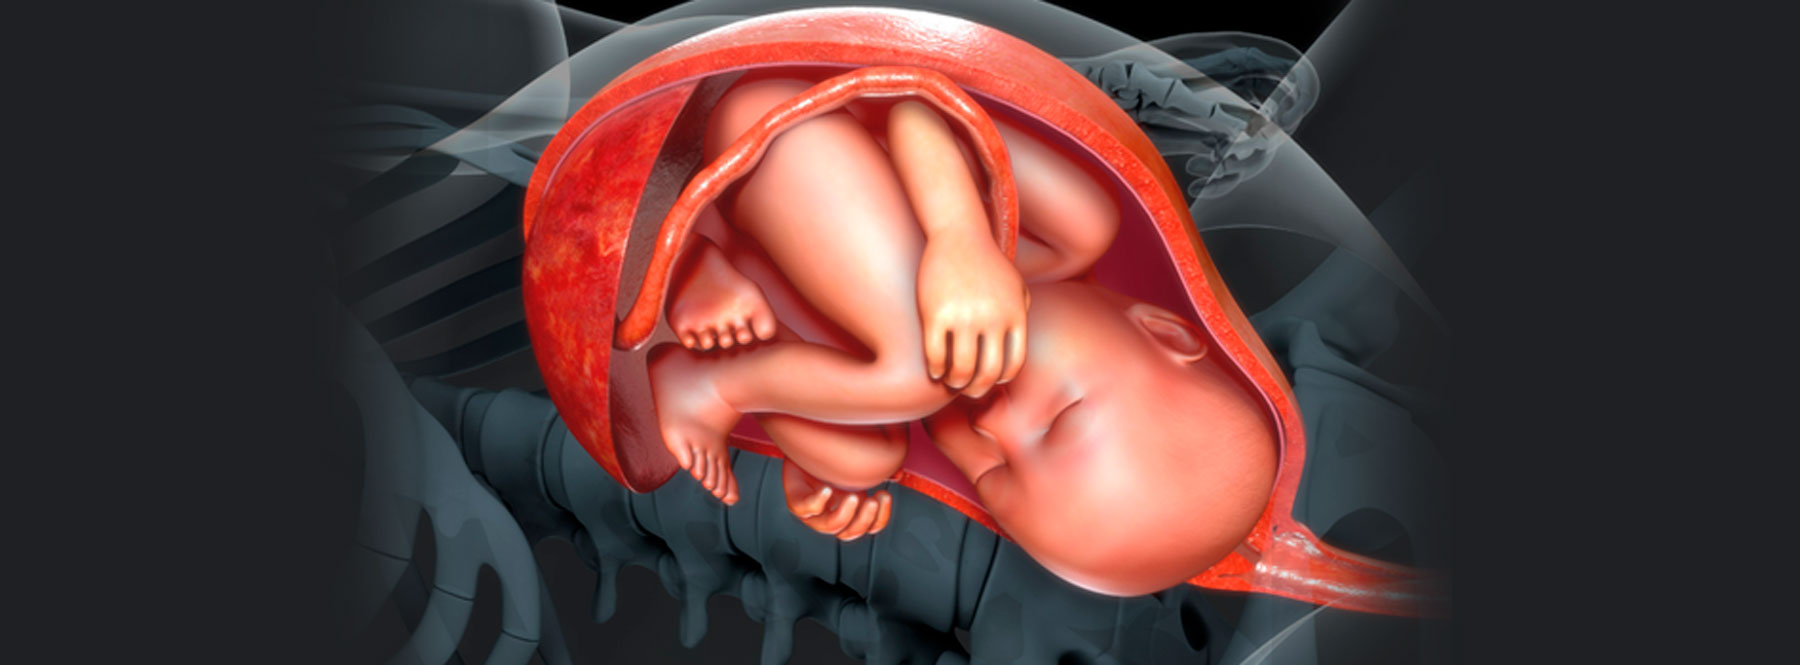

ESPECIALIZACIÓN EN Medicina Materno Fetal

La Especialización en Medicina Materno Fetal es un programa de segunda especialidad que se desarrolla en convenio con la Clínica Universitaria Colombia. El programa tiene como misión formar especialistas con una visión integral en la valoración clínica, diagnóstico, tratamiento y seguimiento de las gestantes en condición de alto riesgo, fomentando el desarrollo de la investigación, el aprendizaje y la docencia que contribuyan a mejorar la problemática de salud en el área y el desarrollo de políticas de salud, que impacten en la calidad de vida de las pacientes y sus familias.

¿Por qué estudiar la Especialización en Medicina Maternofetal?